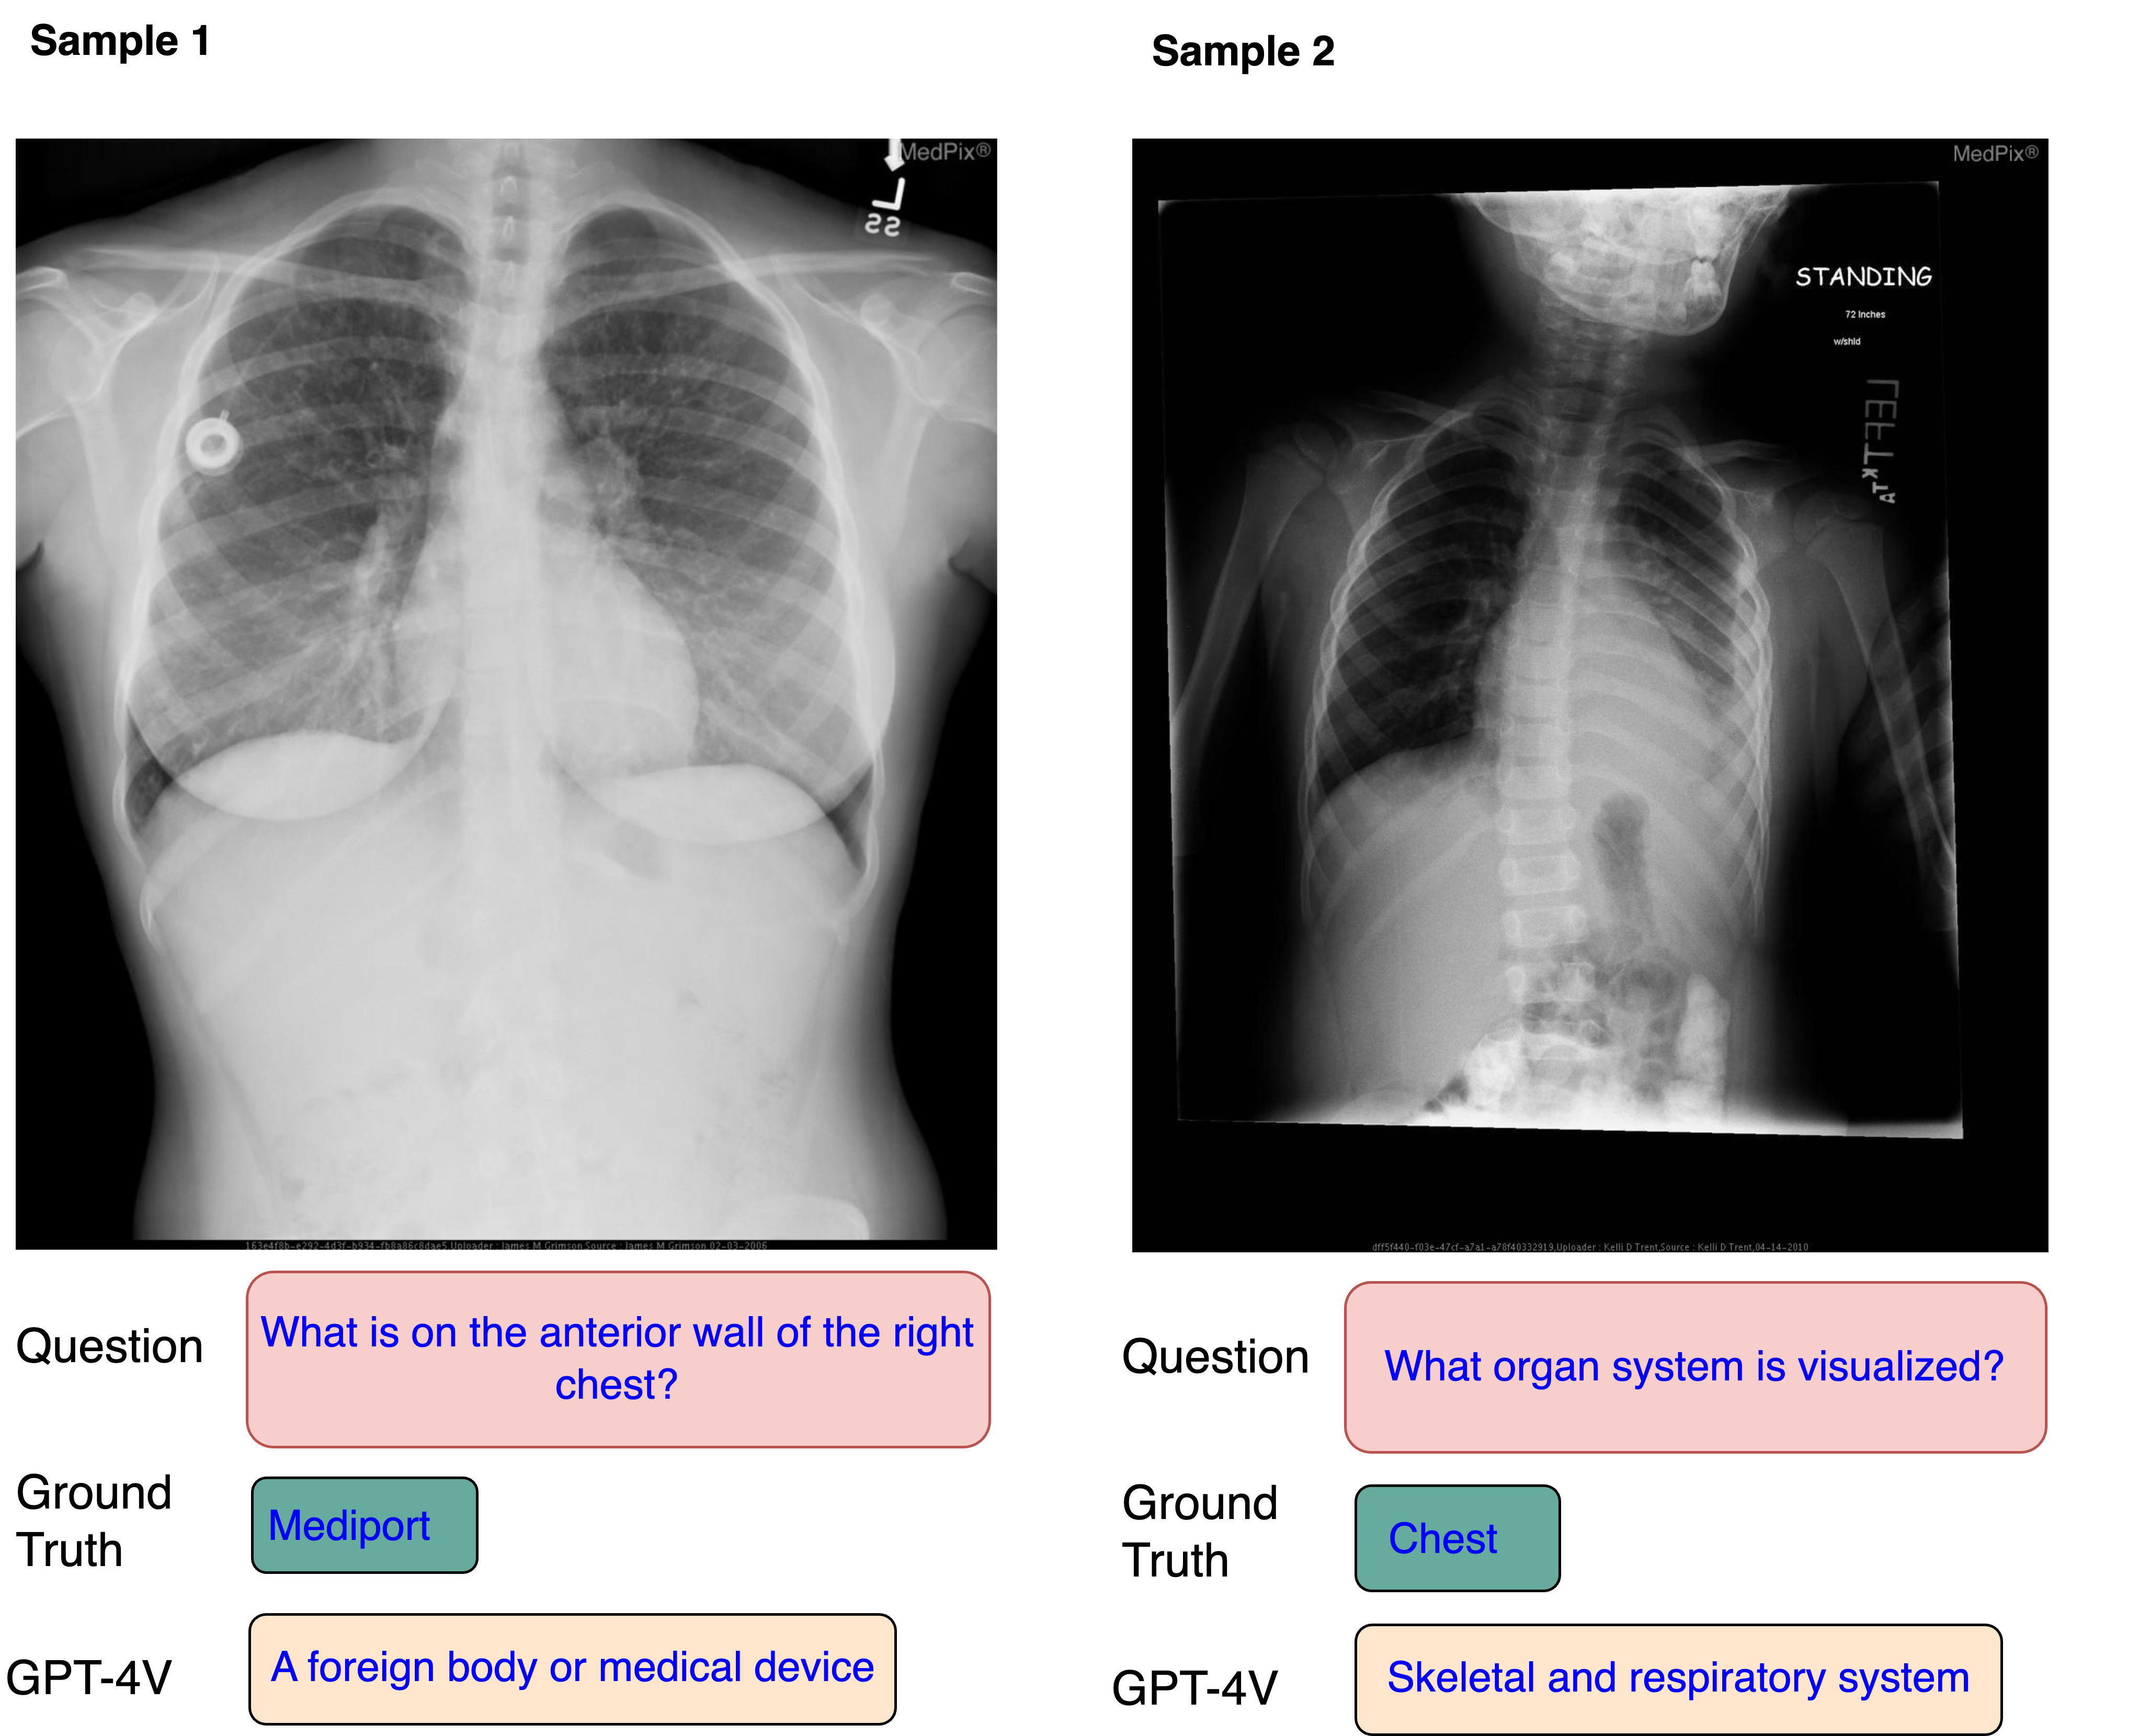

Fig. 9: Two examples showcase GPT-4V’s performance on open-end questions.

Moreover, delving into the answers generated by GPT-4V, the radiologist finds GPT-4V not only matches but surpasses the accuracy of the ground truth. This superiority is attributed to the detailed and precise nature of GPT-4V’s responses. Figure  9 provides two VQA examples produced by GPT-4V. In the right example, given the question “what organ system is visualized”, the ground truth provided only mentions the chest, which is neither rigorous nor sufficient. In contrast, GPT-4V’s response includes the skeleton and respiratory system, demonstrating improved accuracy and completeness. Moreover, the answers generated by GPT-4V exhibit a higher level of generalization and comprehensiveness. As shown in the left example, GPT-4V describes “mediport” as “A foreign body or medical device”. Additionally, GPT-4V produces answers that are more professional and readable, presenting complete sentences with medical terminology and grammatical accuracy. These findings suggest that GPT-4V holds significant learning potential, inviting further exploration through additional research.